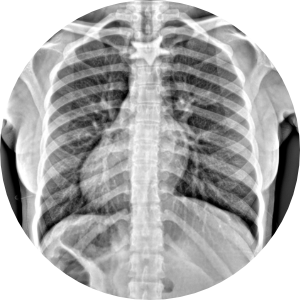

Humanos

• Niños

• Adultos

• Pacientes geriatras

• Seguimiento post cirugía ortopédica

HumanosRadiología Digital Directa

Posteriormente la radiología computarizada evolucionó a la radiología digital directa en donde podíamos hacer placas radiográficas y ver las imágenes en aproximadamente 18-20 segundos después de tomar la radiografía, y esto fue un gran avance para la comunidad de médicos, veterinarios, antropólogos, restauradores, paleontólogos, investigadores, y gente que requería radiografías y que por la logística que se requería y lo que implicaba no utilizaba esta herramienta de diagnóstico. En la actualidad, en la era de la inmediateidad podemos tomar placas radiográficas de alta definición en 2-3 segundos, en lugares remotos, sin necesidad de energia electrica ya que los generadores de rayos X funcionan con baterías, así como los equipos de radiología digital directa, esto ha permitido que el servicio de radiología se pueda proporcionar en cualquier lugar donde se requiera, pudiendo llevarse a donde están los pacientes u objetos a radiografiar, con las ventajas que esto implica. Los equipos actuales son ligeros, portátiles, de alta frecuencia, de alta definición, se ha optimizado la radiación que generan, lo que permite obtener imágenes radiográficas de muy buena calidad, con técnicas radiográficas inferiores a lo que se requería con radiología análoga. Hoy en día manejamos radiología digital directa de alta resolución.

Ideal para pacientes con incapacidad para trasladarse al hospital o moverse. Fracturados, con fijación externa, osteoporosis, niños, adultos, pacientes geriatras, seguimiento post cirugía ortopédica.